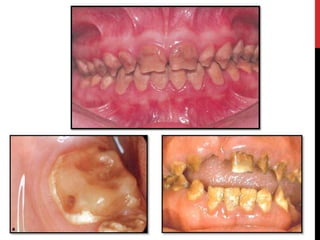

Hypoplastic amelogenesis imperfecta:

Basic alteration centers on inadequate deposition of enamel matrix.

• Generalized pattern

• Localized pattern

• Autosomal dominant smooth pattern

• X- linked smooth pattern

• X-linked rough pattern

Hypomaturation amelogenesis imperfecta

 Enamel matrix is laid down appropriately & begins to mineralize.

 There is defect in maturation of enamel crystal structure.

• Pigmented pattern

• X linked pattern

• Snow-capped pattern

Hypocalcified amelogenesis imperfecta

 Enamel matrix is laid down properly but no significant

mineralization occur.